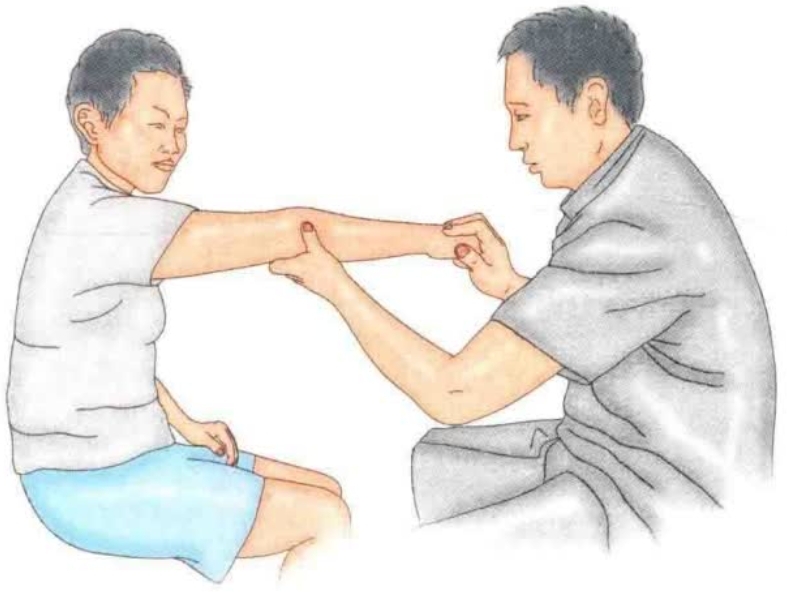

(1)抗阻伸腕试验:伸肘位前臂旋前腕关节抗阻背伸时可诱发疼痛(图2)。

图2 抗阻伸腕试验

(2)牵拉试验:伸肘位腕关节做最大程度掌屈及前臂抗阻旋后时会诱发疼痛(图3)。

图3 牵拉实验